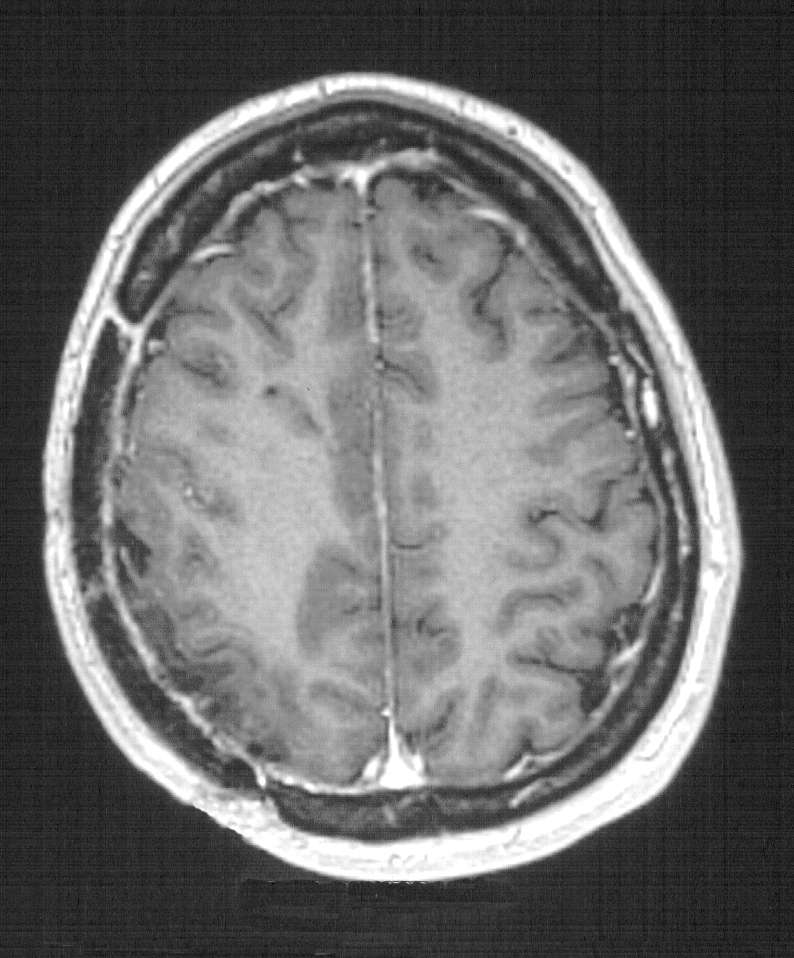

Figura

2. TC encefalica nella seconda giornata post-operatoria.

Modesta falda ematica extradurale di tipo ex-vacuo. RM encefalo a

qualche mese di distanza dall'intervento di cranioplastica.

Completa riespansione parenchimale con scomparsa della falda

ematica sottotecale. |